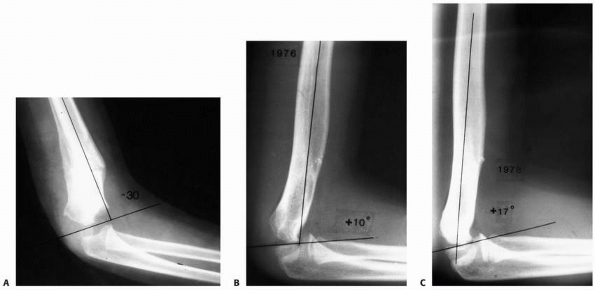

Baumann angle, also referred to as the humeral capitellar angle, is the

angle between the long axis of the humeral shaft and the physeal line

of the lateral condyle (normal range, about

9 to 26 degrees) (Fig. 14-15). A rule of thumb is that a Baumann angle of at least 10 degrees is acceptable; a decrease in the Baumann angle is a sign that a fracture is in varus angulation.

![]() |

FIGURE 14-15

The Baumann angle is between the line perpendicular to the long axis of the humeral shaft and the physeal line of the lateral condyle. A decrease in the Baumann angle may indicate medial comminution. (From Tolo VT, Skaggs DL, eds. Master Techniques in Orthopaedic Surgery: Pediatric Orthopaedics. Philadelphia: Lippincott, 2007:1-15, with permission.) |

sagittal deformity. Restoration of the Baumann angle (which is

generally >10 degrees) on the AP view, intact medial and lateral

columns on oblique views, and the anterior humeral line passing through

the middle third of the capitellum on the lateral view are indications

lateral, and oblique planes. Good reduction is indicated by (i) an

anterior humeral line that intersects the capitellum, (see Fig. 14-14), (ii) a Baumann angle of more than 10 degrees (see Fig. 14-15), and (iii) intact medial and lateral columns on oblique views (Figs. 14-33 and 14-34).